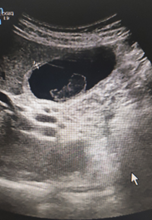

ECOGRAFIA CLÍNICA: Se aprecia vesicular biliar bien repleccionada con imagen en su interior redondeada, hipoecoica, sin sombra, Murphy ecográfico positivo.

Lo llamativo para mi del caso fue visualizar un calculo biliar sin sombra (calculo blando) , saber de su caracteristicas ecograficas y tenerlo como opción diagnóstica.